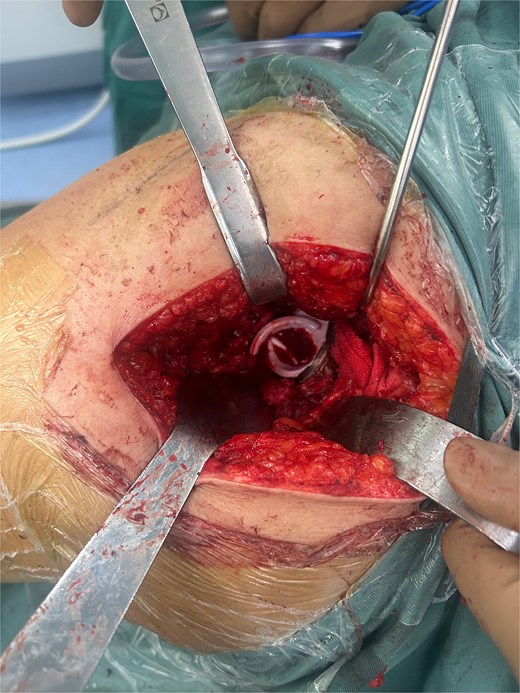

A 47-year-old woman, weighing 65 kg with a height of 158 cm and a body mass index (BMI) of 26 kg/m2, came to our hospital with chief complaints of bilateral hip pain and difficulty walking for 1 year and underwent left THA and 1 week of right THA because of bilateral avascular necrosis and collapse. X-ray of the pelvis of both hips revealed bilateral avascular necrosis and collapse (Fig. 1). A posterolateral approach was used for the bilateral hips in the lateral decubitus position. The implant consists of a Pinnacle cup (DePuy), DELTA ceramic liner and ceramic femoral head (BIOLOX DELTA), and collarless Corail stem (DePuy). After fixation of the acetabular cup, the senior surgeon placed the ceramic liner into the metal shell by hand. Unfortunately, the liner was not placed in the centre position and became stuck. The edge of the tilted ceramic is slightly greater than the cup, perhaps only 5 mm or less. The surgeon attempted to remove the liner by tamping the edge with the plastic impactor using light force several times, but the process of doing so fractured the ceramic liner (Fig. 2). The alumina ceramic fragment of the liner was removed carefully (Fig. 3), and the site was irrigated well. A 32-mm polyethylene liner and a ceramic femoral head were implanted. Full weight-bearing was allowed on postoperative day 1 with a walking aid. The patient remained hospitalized for 8 days to monitor closely for early perioperative complications. Sutures were removed on the seventh day, and the laboratory results indicated an absence of infection. At the 2-month postoperative interval, the patient achieved a successful outcome, with complete resolution of her preoperative symptoms as well as a return to all her activities of daily living (Fig. 4).

A radiograph was obtained preoperatively of a 47-year-old woman with bilateral avascular necrosis and collapse.